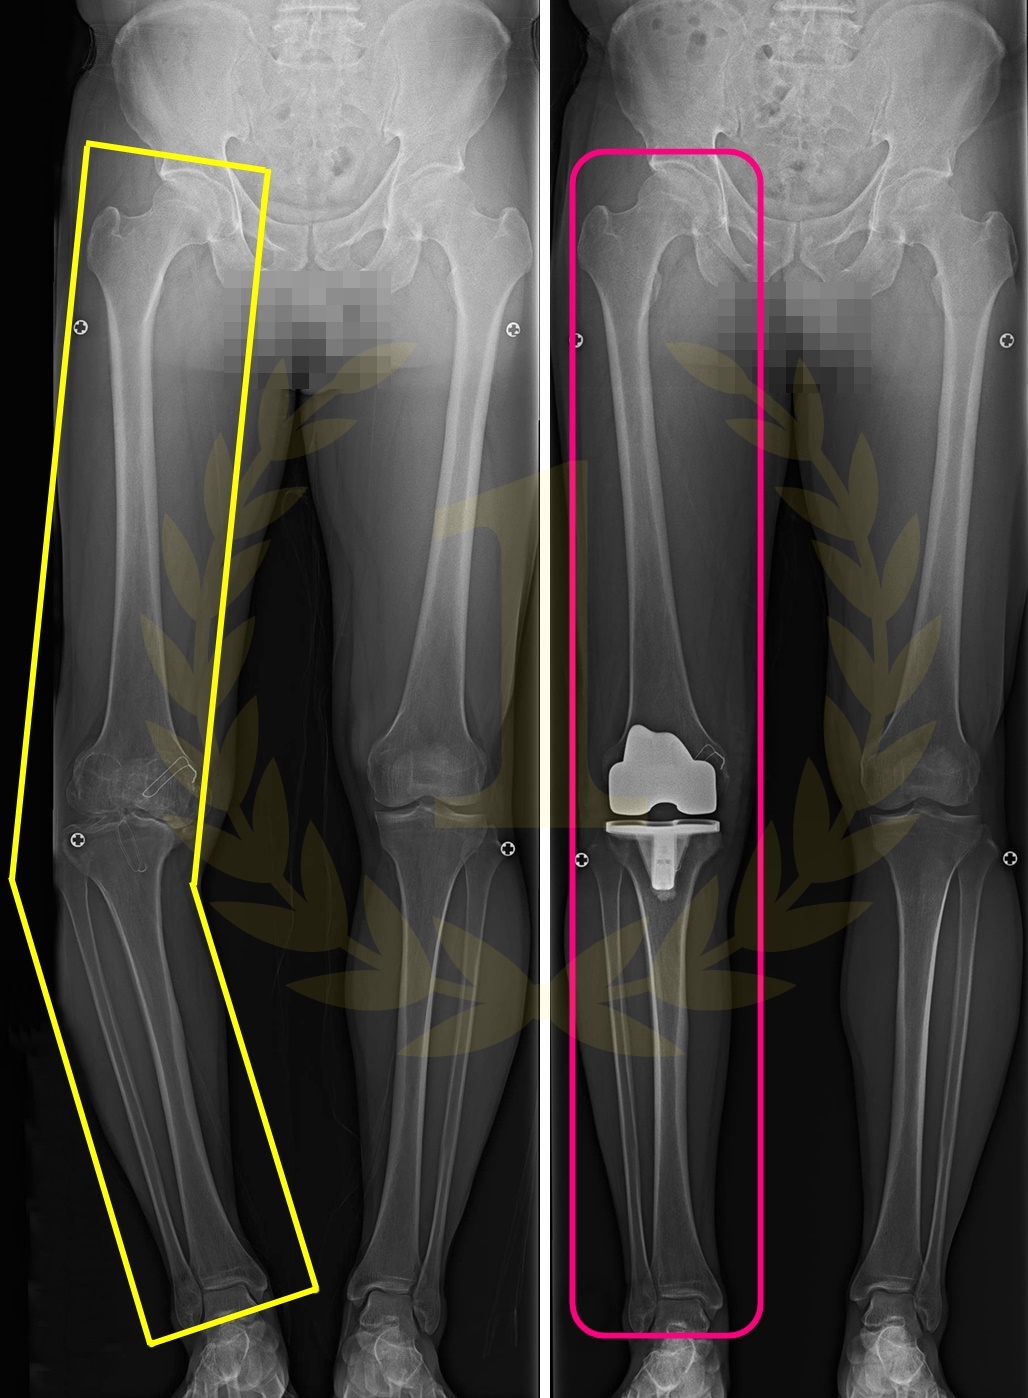

사지연장 및 변형교정

키수술ㅣ휜팔다리ㅣ휜손발가락ㅣ단지증ㅣ장지증

무지외반증ㅣ까치발ㅣ요족ㅣ족하수ㅣ소아마비